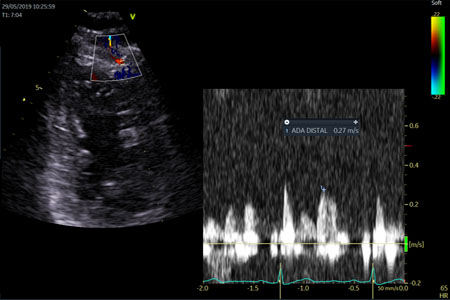

El Doppler pulsado en la arteria descendente anterior distal registra una reducción muy significativa de la velocidad respecto al registro más proximal (28 cm/seg). Dicho gradiente sugiere obstrucción significativa.

Vistas comparativas de los flujos Doppler de DA distal en el estudio inicial isquémico a la izquierda y en el estudio post tratamiento a la derecha.

Normalización del perfil de velocidad de flujo de la arteria descendente anterior distal post tratamiento.